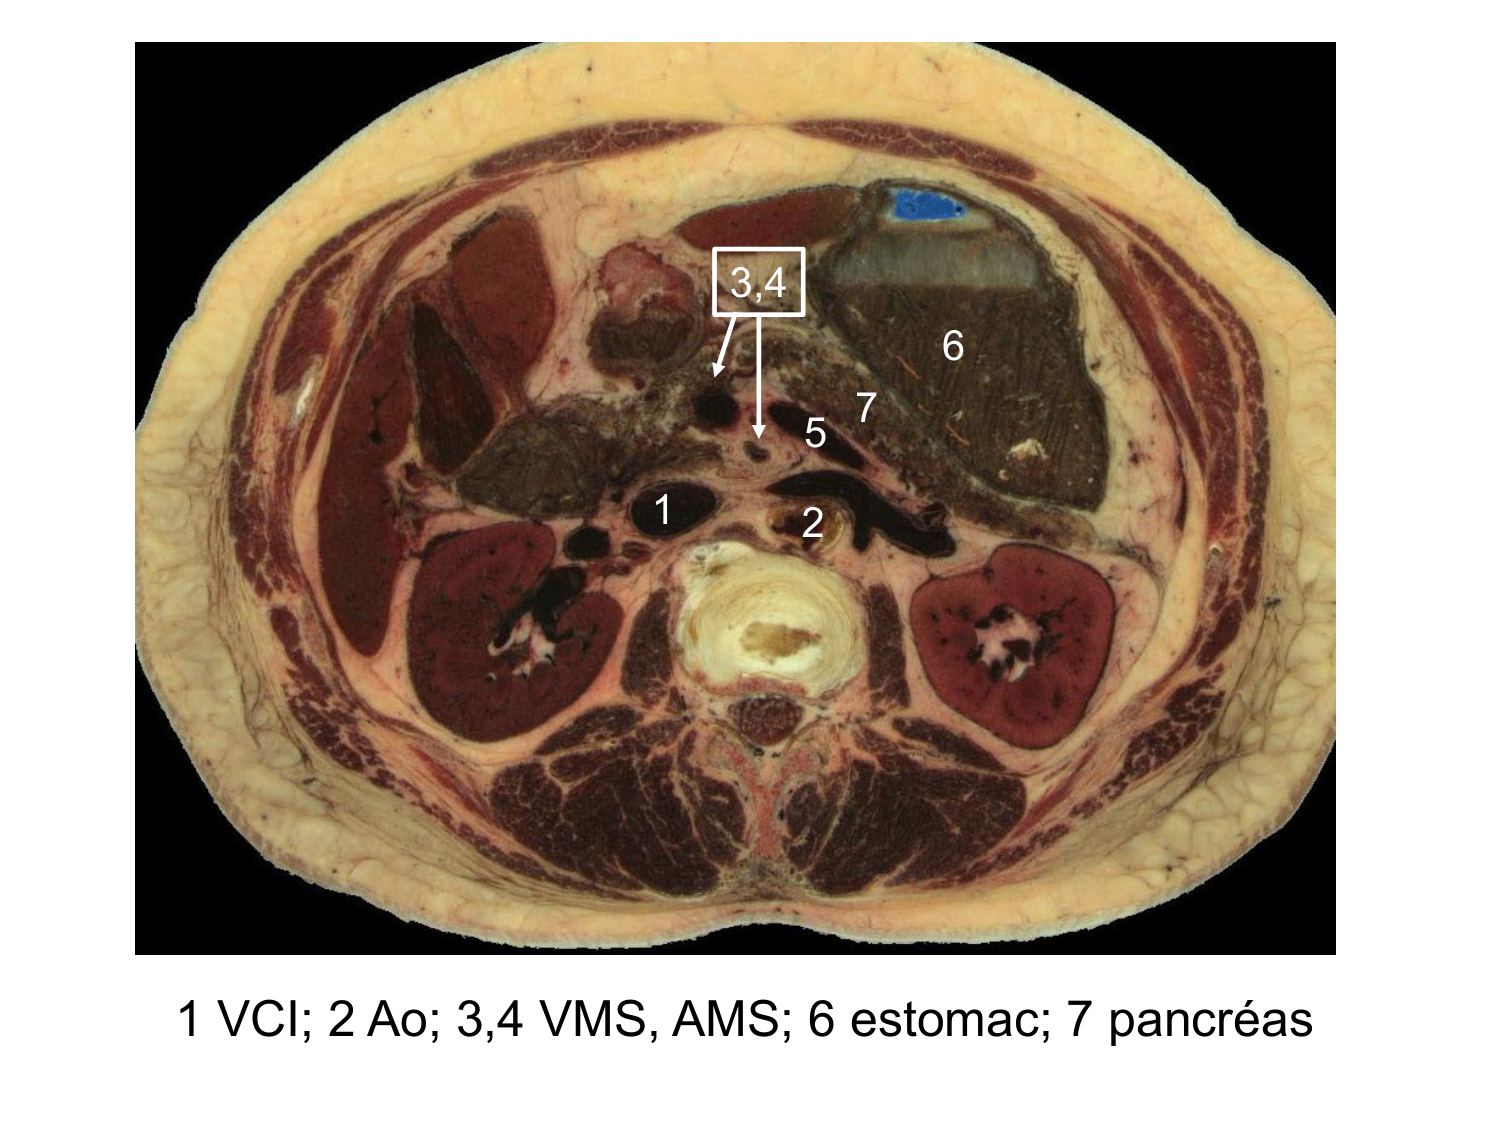

Anatomie du système endocrinien2

Bases de l'anatomie · 92 pages · 12 sections